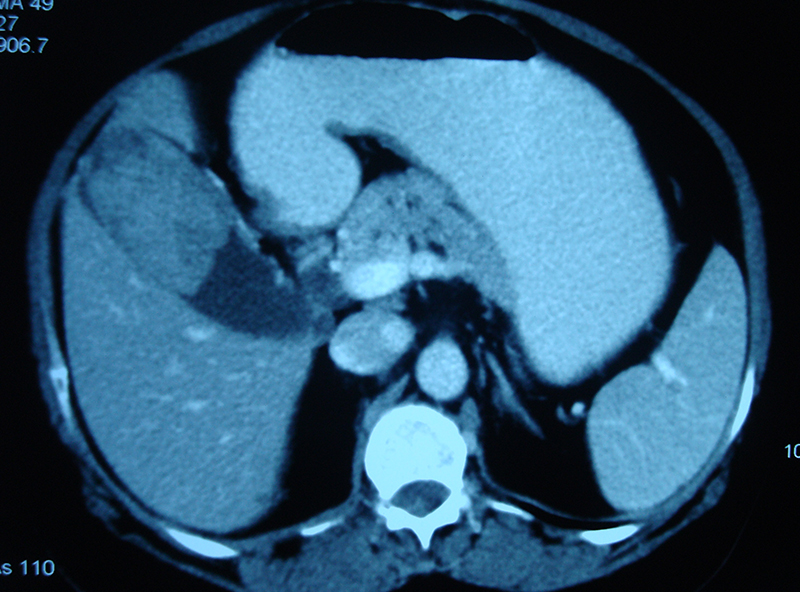

45 year old lady with abdominal pain, loss of appetite and weight was diagnosed on investigations to have a large gall bladder mass. She underwent a curative radical resection involving the gall bladder, part of liver, bile duct and lymph nodes. The bile duct was joined to a loop of intestine. The opened specimen of gall bladder showed a large mass and multiple gall stones. The mass was a gall bladder cancer (adenocarcinoma) on final histopathology. Patient continues to live happily for more than 5 years after surgery without any chemotherapy. To know more about gall bladder cancer click here